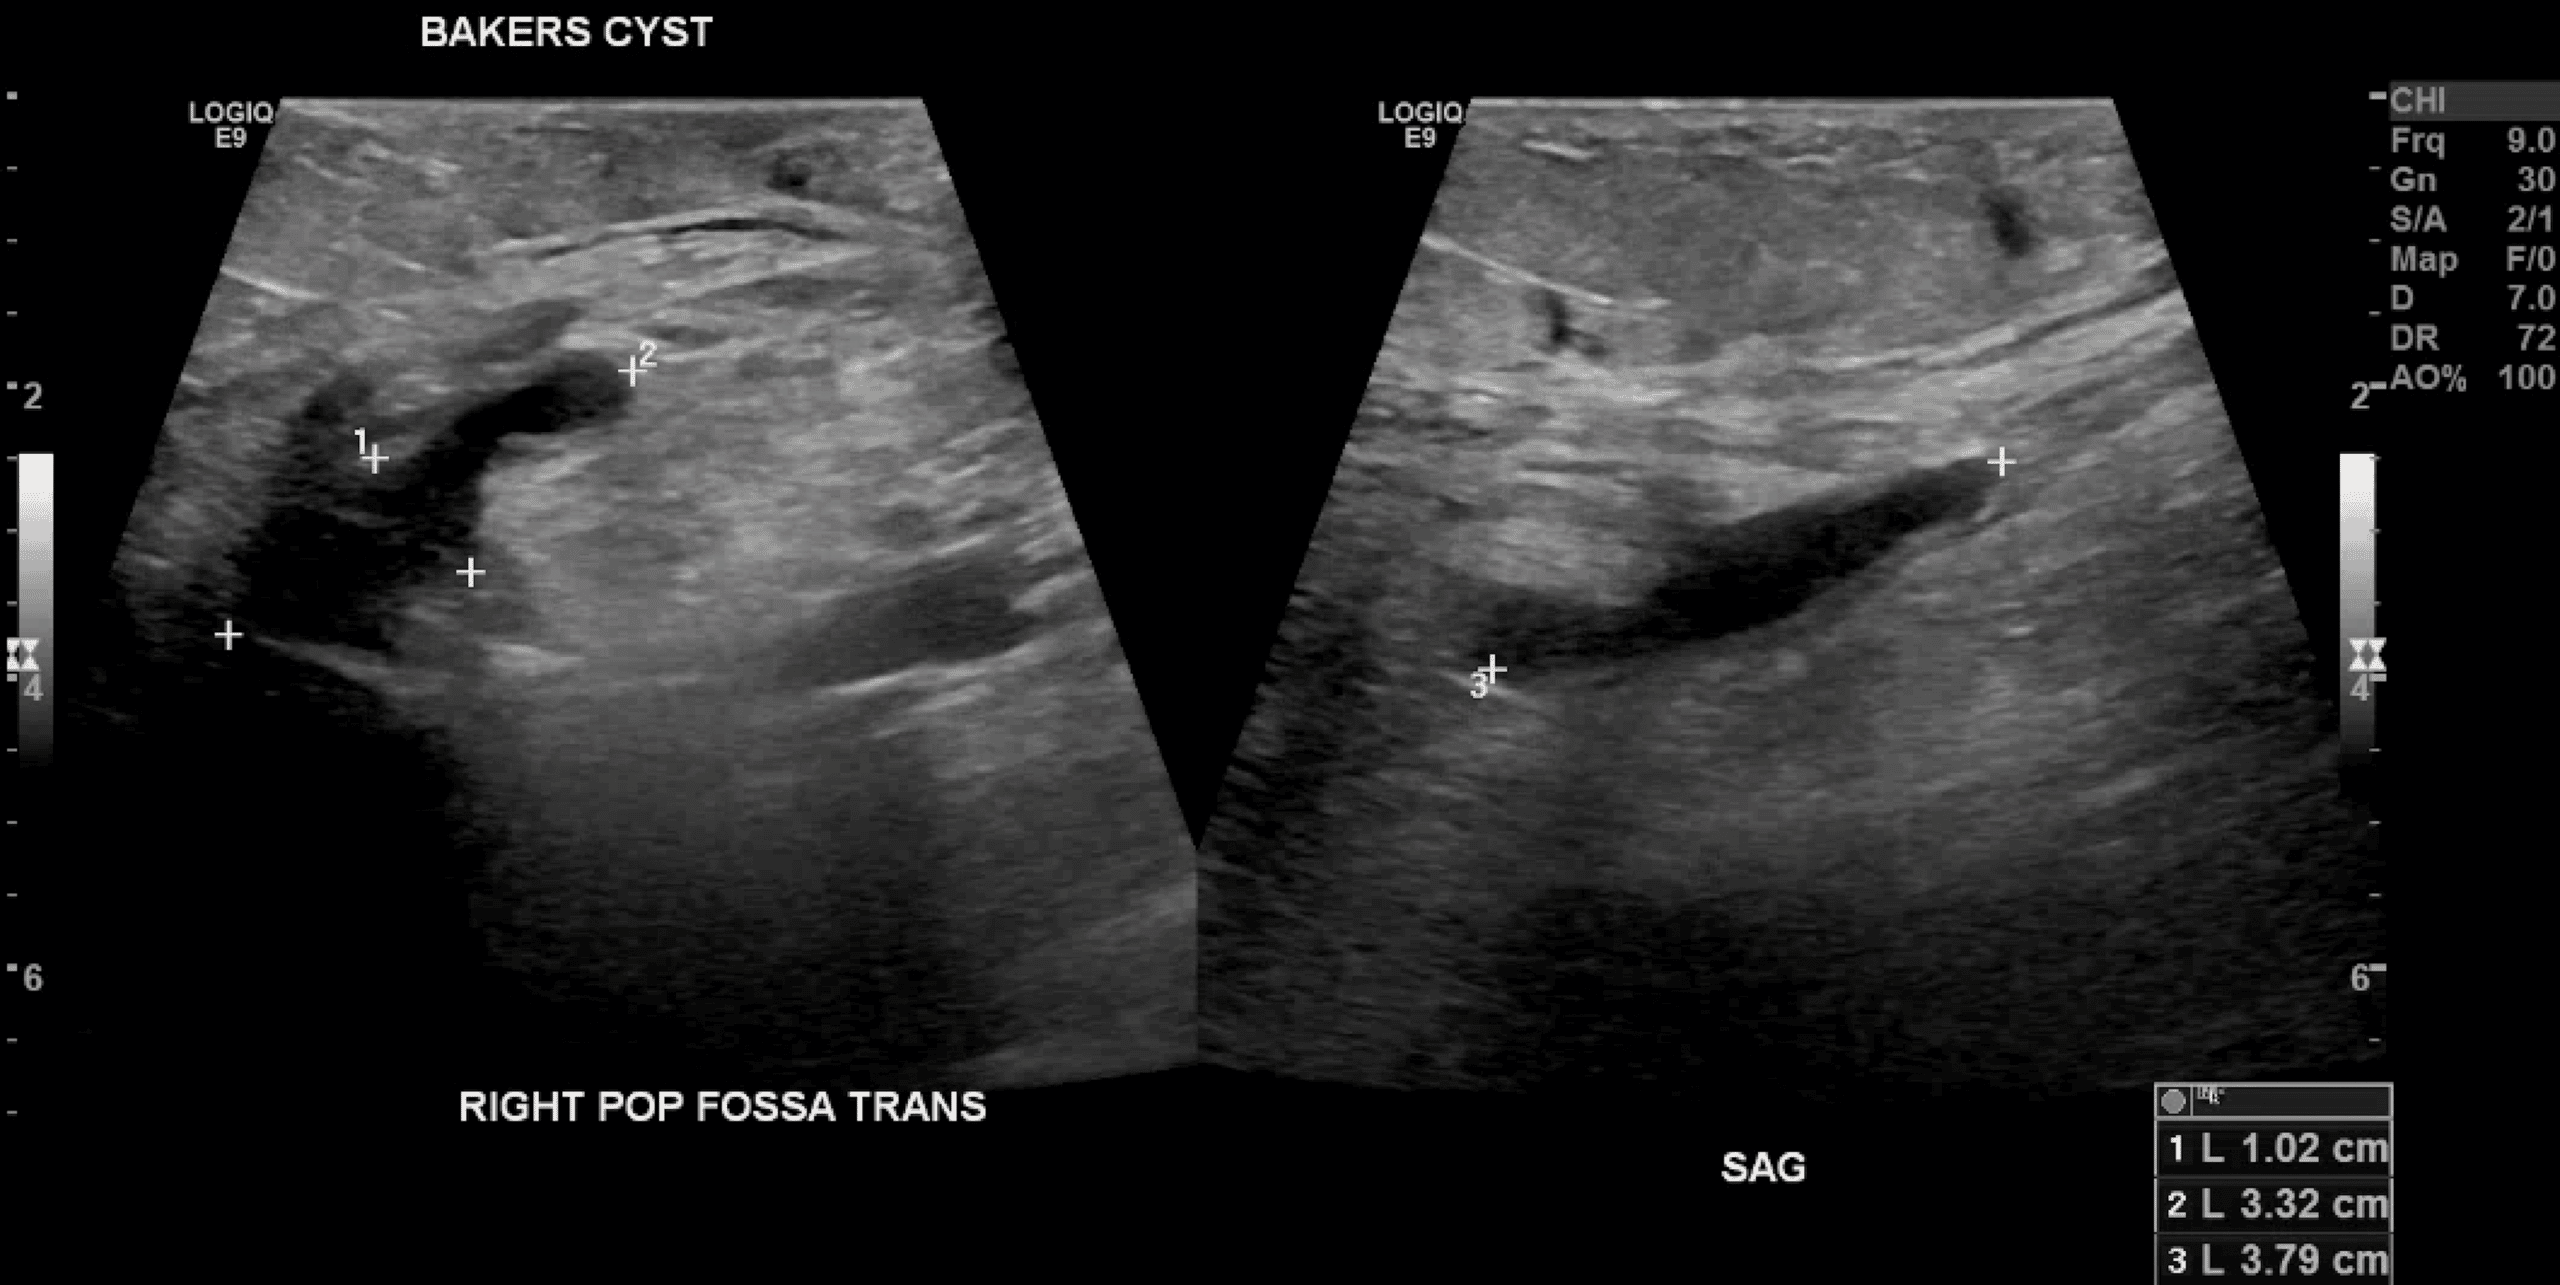

A Baker’s cyst is a fluid collection that forms in the bursa between the gastrocnemius and semimembranosus muscles. Ultrasound is most commonly used:

There are not many other reasons for such a fluid collection. But (ultrasound) reader beware! Masses behind the knee can look like cysts on ultrasound. A popliteal artery aneurysm can look like a small fluid collection as well. You have to make sure that there is no blood flow within the collection. Also, think about further imaging if anything does not fit a typical cyst. For instance, septations are allowed in a popliteal cyst. But if there are many septations or if the shape is unusual, it is best to obtain more imaging. For instance, with CT or (more commonly) MRI.